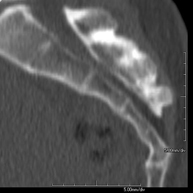

- Sacroiliac CT

Radiological examination based on an X-ray system and detectors that rotate around the patient, reconstructing the images by computer (multidetector computed tomography - MDCT) to study the sacroiliac joints and rule out inflammatory, traumatic or degenerative diseases.